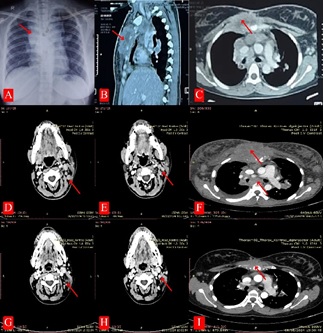

A 27-year-old female with a history of 5 months of enlargement of the left cervical lymph node, which progressed to a neck wound following open biopsy. She additionally reported general weakness, fever, night sweats, anorexia, and weight loss. She possesses no notable medical history and has no known tuberculosis contacts. The biopsy result showed granulomatosis inflammation with necrosis. The Real Time Polymerase Chain Method (PCR) sputum and tissue biopsy results were negative for Mycobacterium tuberculosis. From the initial Chest X-ray, enlargement of mediastinal and Chest CT-scan with contrast showed an abscess colli bilateral, right paratracheal, and superior mediastinal with sternum destruction suggestive of osteomyelitis (Figure 1A and 1B-C).

Figure 1. (A). Early Chest X-ray showed enlargement of the mediastinal; (B) Chest CT-scan with contrast before ATT showed an abscess colli bilateral, right paratracheal, and mediastinal superior with sternum destruction suggestive of osteomyelitis; (C) Re-chest and head-neck CT scan after 4 months ATT revealed a soft tissue mass 5.7 x 9.5 cm infiltrating cutis in the pre-sternal region with the destruction of the sternum and multiple lymph nodes in the thorax, axilla, and cervical area; (D) Improvement of chest and head-neck CT scan after six treatment cycles CHOP chemotherapy, soft tissue mass pre sternal disappeared and the reduce number and size lymph node enlargement in mediastinal and colli.

Lymph node enlargement was also found on the right side of the cervical area, with a diameter of 2 cm, and in the bilateral axilla, 3 cm, firm, not warm, and non-tender. Initial blood tests demonstrated a decrease in haemoglobin to 9.2 g/ dL, an elevated white blood count (WBC) of 19 × 109/L (normal range (NR) 4–10.5 × 109/L) with neutrophilia (84.5%, NR 50-81%), hypoalbuminemia, 2.4 g/dl (NR 3.2-4.6 g/dl) and imbalance of electrolytes [natrium 131 Meq/L (NR 136-145 Meq/L) and kalium 2.5 Meq/L (NR 3.5-5.1 Meq/L)], LDH 351 U/L (NR < 480 U/L) with normal liver and renal function test. Further investigation revealed a soft tissue mass 5.7 x 9.5 cm infiltrating the cutis in the pre-sternal region with the destruction of the sternum and multiple lymph nodes in the thorax, axilla, and cervical area, as observed in the chest and head-neck CT scan (Figures 1D-E). A re-biopsy of the lymph node found anaplastic large cell lymphoma (ALCL) (Figure 2C) as a rare type of Non-Hodgkin Lymphoma with positive Ki67, CD45, and CD3 and negative CD20 and CK. Due to resource constraints at our facility, we cannot conduct the CD30 and ALK examination. The patient also refused a bone marrow biopsy, and a PET-CT scan was not performed for staging follow-up because of limited resources. Finally, the chest multidisciplinary team (MDT) meeting was conducted, and confirmed a diagnosis of classical non-Hodgkin’s lymphoma classified as Ann Arbor stage IVB. Consequently, TB medication was discontinued, and a combination of cyclophosphamide, doxorubicin, vincristine, and prednisone (CHOP) chemotherapy was administered. We cannot give systemic ALCL guidelines (e.g., NCCN) recommend CHOEP (adding etoposide) for fit patients <60 years, or brentuximab vedotin + CHP, because of the limitations of the hospital. After six treatment cycles, the patient’s clinical condition improved with the wound healed, and from chest and head-neck CT scan imaging evaluation showed soft tissue mass pre-sternal disappeared and reduced the number and size of lymph node enlargement in mediastinal and collar (Figures 1G-I, and 2B).